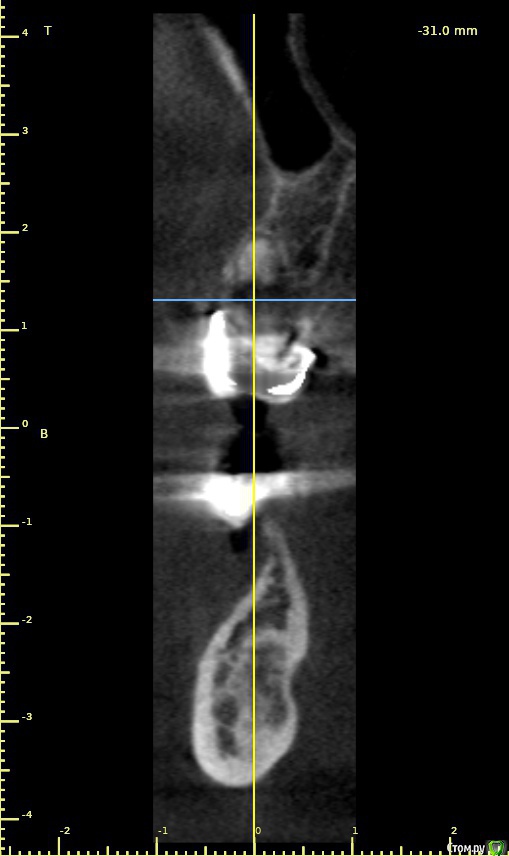

Дмитрий Л. Опубликовано 23 мая, 2018 Поделиться Опубликовано 23 мая, 2018 (изменено) 4 квадрант Судя по срезу кт - костный рисунок, хотелось бы больше срезов. Изменено 23 мая, 2018 пользователем Дмитрий Л. Ссылка на комментарий

Борис80 Опубликовано 23 мая, 2018 Автор Поделиться Опубликовано 23 мая, 2018 какое то образование с четкими границами, достаточно большое, по структуре напоминает кость, но имеет четкий контур...в пределах челюсти, жалоб не предъявляет, с правой стороны(шрам на шее) была резекция подчелюстной слюнной железы, 3д моделировка снаружи: Ссылка на комментарий

Борис80 Опубликовано 23 мая, 2018 Автор Поделиться Опубликовано 23 мая, 2018 были бы более скромные размеры, я бы принял подобное за секвестры, но тут 3 см... Ссылка на комментарий